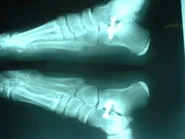

El tratamiento quirúrgico en recurso para corregir el pie plano, cuando ha fallado el tratamiento conservador. Existen muchas técnicas quirúrgicas, pero quizás la que está más difundida es la descrita por el Dr. Recaredo Álvarez en 1972, la técnica de Calcáneo Stop, la cual reconstruye la relación entre los huesos astrágalo calcáneo, sin actuar en superficies articulares, actuando en el seno del tarso constituyendo el concepto llamado artrorrisis, realizada con un tornillo especial de bloqueo.

La técnica de calcáneo stop es un procedimiento quirúrgico sencillo y ambulatorio, el cual permite corregir el pie plano valgo juvenil (8 a 12 años de edad), con excelente resultados. El paciente inicia el apoyo a las 24 horas, tendiendo a caminar metiendo los pies, lo cual es normal en las primeras semanas del postoperatorio, lo padres no deben preocuparse por este hecho.

Preoperatorio pie plano valgo

paciente de 10 años

Postoperatorio 4 semanas

Caso clínico: Paciente de 10 años de edad, quien presentaba pie plano valgo doloroso, con acortamiento del tendón de Aquiles (gemelos). Fue intervenido quirúrgicamente practicándose  cura operatoria según la técnica de calcáneo stop, con la colocación de tornillo de bloqueo en el seno del tarso y alargamiento del tendón de Aquiles según técnica de Vulpius. Excelente resultado postoperatorio. Ver imágeness arriba y a la derecha.

Postoperatorio. Vista posterio del pie.